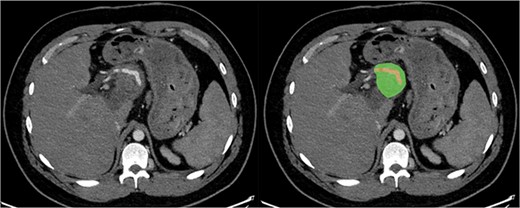

Due to the debilitating nature of the patient’s condition and his wishes for an attempt at treatment, he was brought forward for a further exploratory laparotomy. The patient’s rooftop incision was reopened and the wound and sinus tract were excised en bloc. The stomach and transverse colon were found to be densely adherent to the teratoma. These were carefully mobilized and dissected free from the teratoma. Again, resectability of the teratoma was assessed and deemed to be impossible due to the hepatic artery being inseparable from the lesion (Fig. 2). Instead, internal drainage with diversion of the sinus discharge via a jejunostomy with a Roux en Y reconstruction of the alimentary tract was performed. The jejunum was divided at 50 cm from the duodenojejunal (DJ) flexure and the Roux limb was brought up to the origin of the sinus through a window made in the mesentery of the transverse colon. The lumen was opened and sutured over the origin of the sinus with 4/0 PDS sutures (Fig. 3). Finally, a jejunojejunostomy was formed to return continuity to the jejunum.

Axial section of CT with arterial contrast showing the hepatic artery (red) traversing within the superior aspect of the lesion (green).